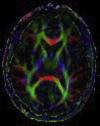

The development of magnetic resonance imaging (MRI) for use in medical investigation has provided a huge forward leap in the field of diagnosis, particularly with avoidance of exposure to potentially dangerous ionizing radiation. With decreasing costs and better availability, the use of MRI is becoming ever more pervasive throughout clinical practice. Understanding the principles underlying this imaging modality and its multiple applications can be used to appreciate the benefits and limitations of its use, further informing clinical decision-making. In this article, the principles of MRI are reviewed, with further discussion of specific clinical applications such as parallel, diffusion-weighted, and magnetization transfer imaging. MR spectroscopy is also considered, with an overview of key metabolites and how they may be interpreted. Finally, a brief view on how the use of MRI will change over the coming years is presented.